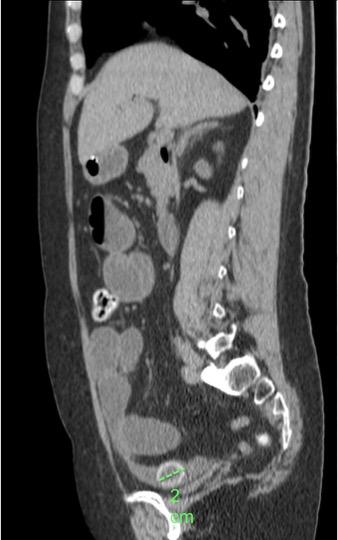

Se realiza un TC abdominal sin contraste:

Observar como posterior a la litiasis hay un cambio de calibre, el segmento que queda de ileon y el colon no están distendidos.

No encontramos ante un Ileo biliar, una obstucción intestinal mecánica ocasionada por una litaisis enclavada en el íleon terminal. La paciente estaba colecistectomizada, por tanto, lo más probable es que haya sido producido por una litiasis residual que pasó desapercibida.

Se realiza una TC con contraste en fase portal con cortes de 3 mm y cortes finos para realizar reconstrucciones. Puede realizarse sin contraste para poner más de manifiesto la litiasis cálcica. La información obtenida por TC nos permite un diagnóstico rápido y preciso, además de ser una ayuda muy preciada para el cirujano a la hora de decidir el tratamiento a realizar.

- Litiasis (2 – 3 cm aprox). Hay que tener cuidado ya que muchas litiasis no están calcificadas y su densidad puede ser similar al contenido del intestino. Pueden ser multiples, por tanto hay que poner atención para que no pasen desapercibidas y evitar las recidivas.